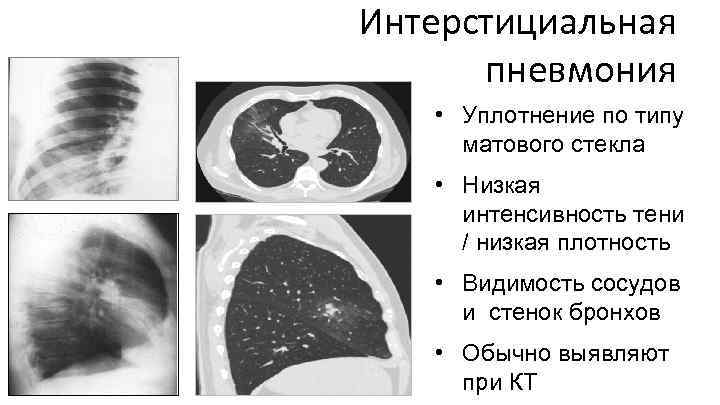

Интерстициальная пневмония • Уплотнение по типу матового стекла • Низкая интенсивность тени / низкая плотность • Видимость сосудов и стенок бронхов • Обычно выявляют при КТ